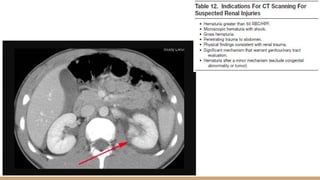

• #10 This is CT Scan Abdominal, the red arrow showed pedicle shattered of the left renal